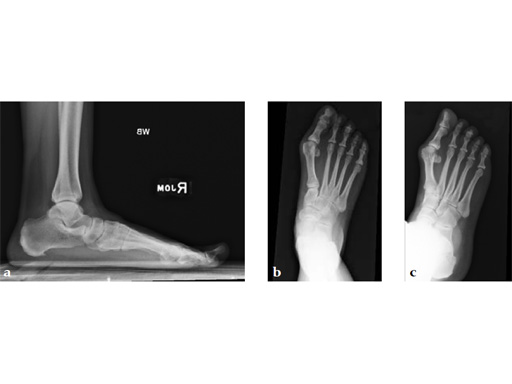

Case 8: VA -locking X-plate

A 38-year-old man fell from a 7-foot height while at work. The patient was seen at an urgent care facility and diagnosed with an ankle sprain. He was placed in a stirrup brace and instructed to bear weight as tolerated.

Case provided by Michael Castro, Scottsdale, Arizona

After 4 months the patient presented for a second opinion. His complaint was pain to the lateral column and subtalar joint. The preoperative lateral x-ray is notable for a malunited talar neck fracture with subluxation of the subtalar joint. The disproportion of the medial and lateral columns and a cavovarus position of the foot are seen on both the AP and lateral views. The degenerative changes at both the talonavicular and subtalar joints are significant.

The patient was treated with arthrodesis of the talonavicular and subtalar joints. The compression/ distraction device was used to restore the length of the medial column. The articular surface of the subtalar joint was prepared arthroscopically. The talonavicular joint was debrided then packed with a tricalcium matrix. Length was maintained using a locking X-plate. The subtalar joint was then fixed with a 6.5 mm headless compression screw.

The patient returned to work 3 months after surgery. He wears an ankle brace when on uneven surfaces. His lateral column and subtalar pain have resolved.